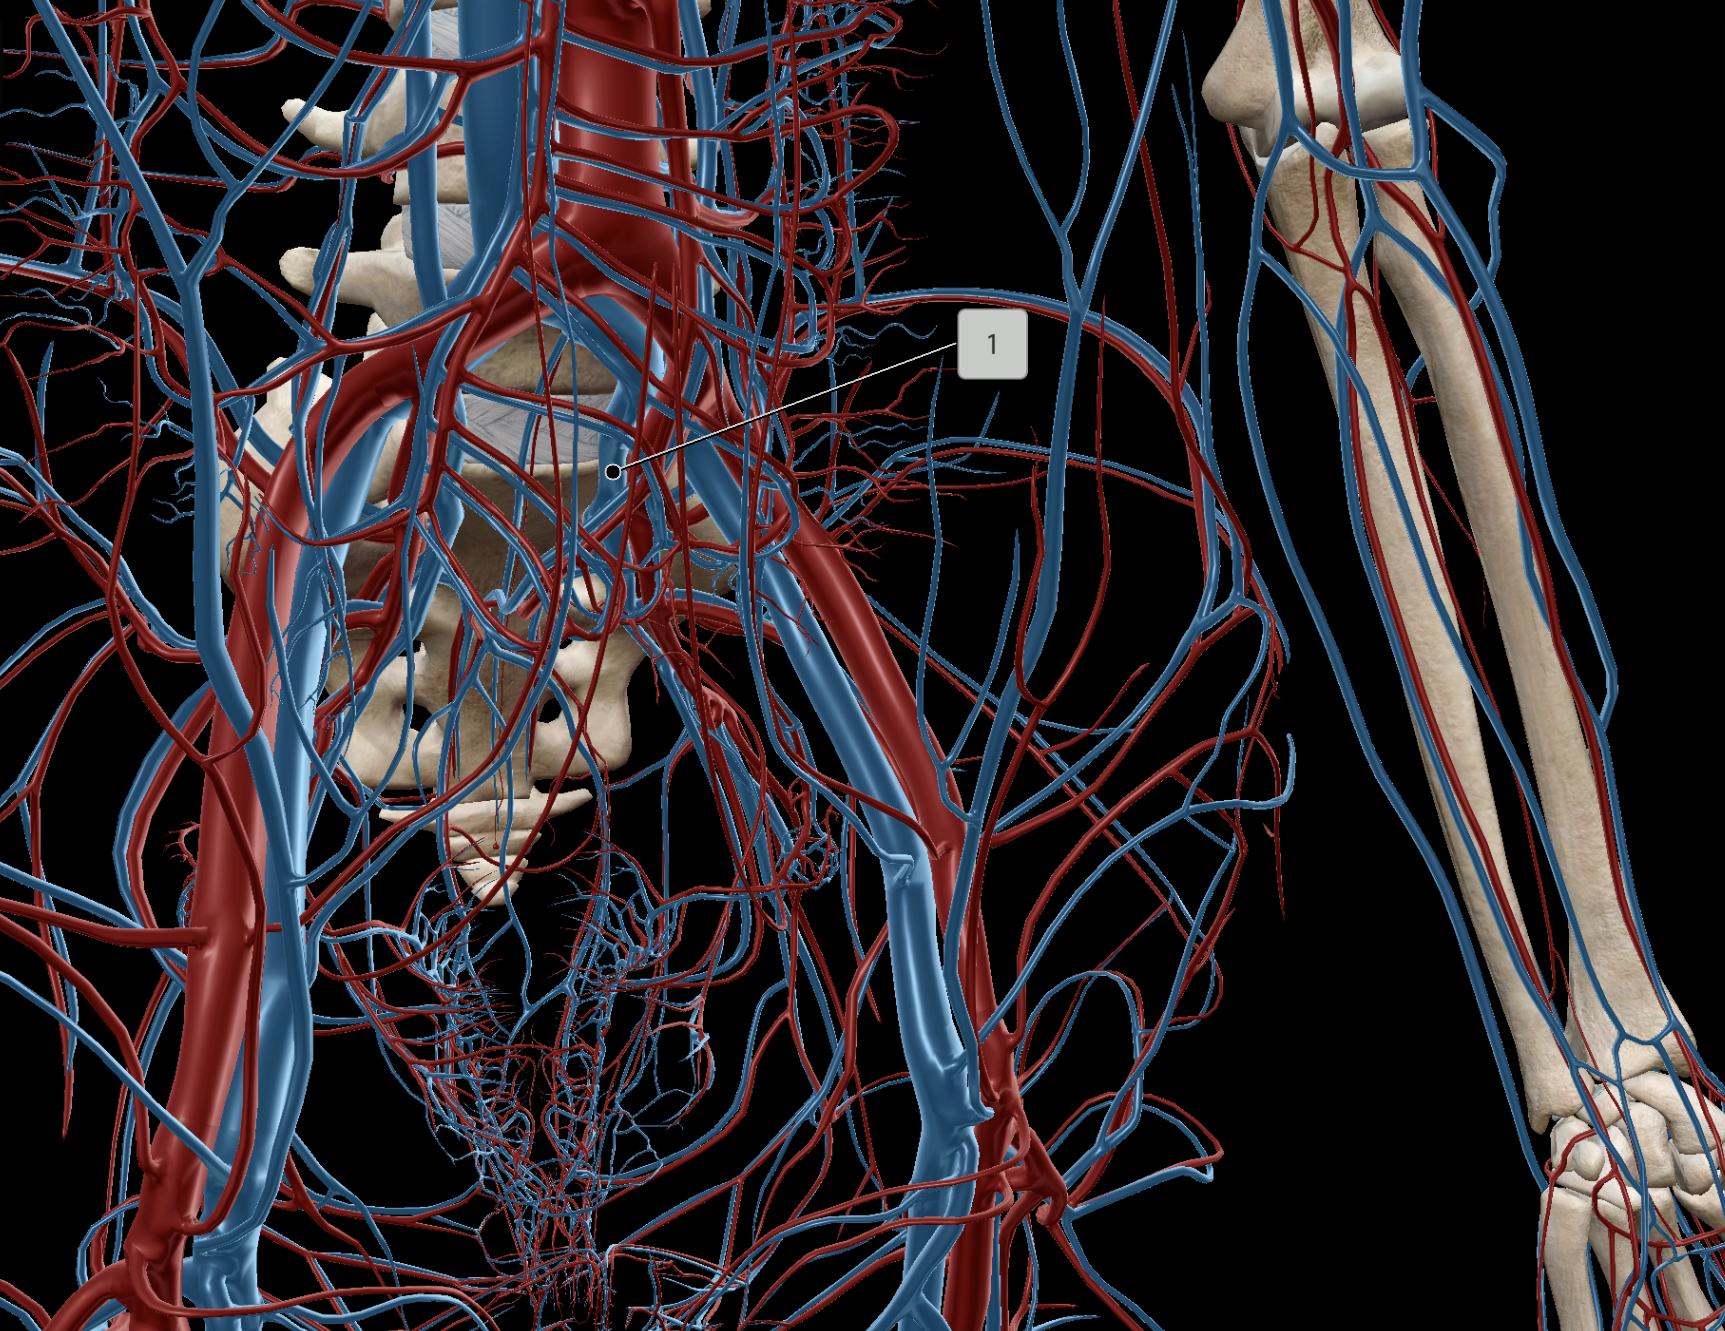

Inferior Vena Cava

Common Iliac Artery

Internal Iliac Artery

External Iliac Artery

Abdominal Aorta

Common Iliac Vein

External Iliac Vein

Internal Iliac Vein